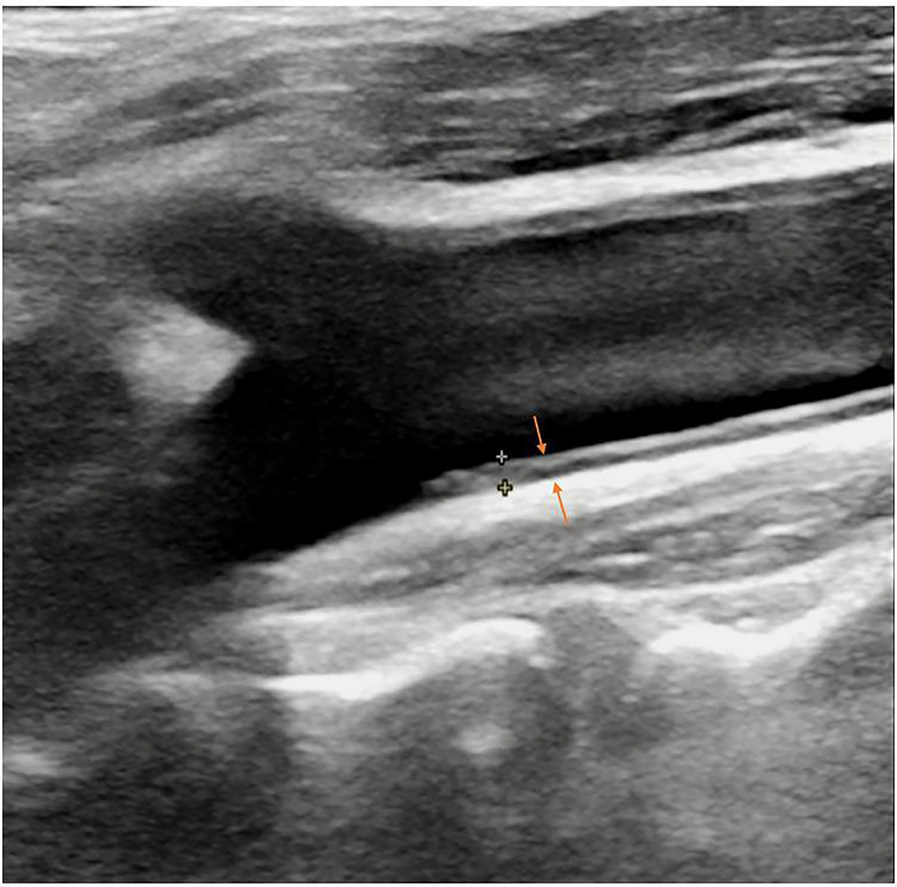

Figure 3

B-mode ultrasound image of carotid intima-media thickness (IMT) (arrows).